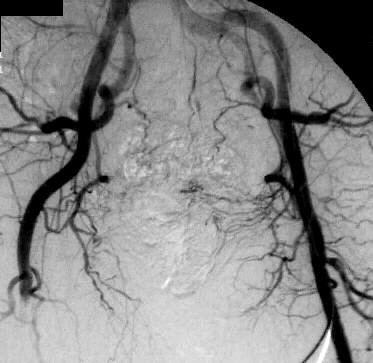

the pathological image-left and the physiological image-right

Adult woman, 73-years-old

- history of atrial fibrillation, but the patient refuses any medication. Physical

examination reveals a pale, pulseless and painful right leg.

D:

Acute embolism of

the superficial femoral artery at the right side caused by atrial fibrillation